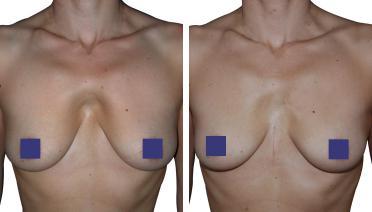

Petto Escavato: risultati prima e dopo

In questa pagina, troverà i risultati di questa operazione a seconda del tipo di Pectus : mediale, asimmetrico, più o meno profondo o lungo.

Tipo 2 : Ampio, poco profondo e simmetrico,